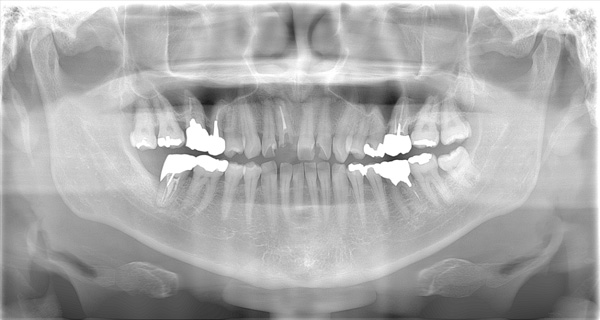

AFTER

| 年代・性別 | 50代 男性 |

|---|---|

| 主訴 | 右下の歯がないのでインプラントをして欲しい |

| 治療期間 | 約6ヶ月 |

| 費用 | 600,000円 |

| 治療内容 | インプラント、骨造成、結合組織移植、セラミック修復 |

| 治療に伴うリスク | インプラント周囲炎 セラミックの破折、脱離 |